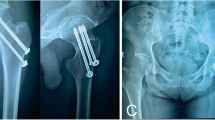

Based on the Pauwels angle measured before operation, the patients were categorized into three groups: Group A (Pauwels angle < 30°), Group B (Pauwels angle > 30° and < 50°), and Group C (Pauwels angle > 50°). Furthermore, each of these groups was subdivided into three categories based on the reduction quality: anatomical reduction group, positive buttress group, and negative buttress group. Anatomic reduction group: There was no displacement between the inner and upper margins of the distal fracture end and the inner and lower edges of the proximal fracture end. positive buttress group: the inner and lower edges of the distal fracture end protruded medially to the inner and upper edges of the proximal femoral neck fracture end. negative buttress group: the distal femoral neck fracture end protruded medially toward the inner and lower borders of the proximal fracture end. As seen in Fig. 1, groups A1, B1, and C1 are anatomical reduction. Groups A2, B2, and C2 are positive buttress. Groups A3, B3, and C3 are negative buttress.